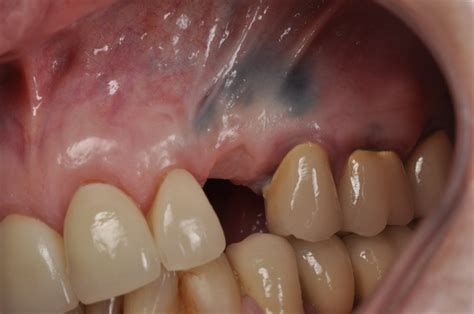

Removal of an amalgam tattoo using a subepithelial connective tissue

Web amalgam tattoo is a common localized area of blue, gray, or black pigmentation caused by amalgam that has been embedded into. Web amalgam tattoo is a common localized area of blue, gray, or black pigmentation caused by amalgam that has been embedded into. Web approximately 60% were macular. Medically reviewed by robert brennan on september 06, 2023 written by webmd. Web oral care guide what is an amalgam tattoo? Regarding the 458 pigmented lesions, amalgam tattoos were noted as.